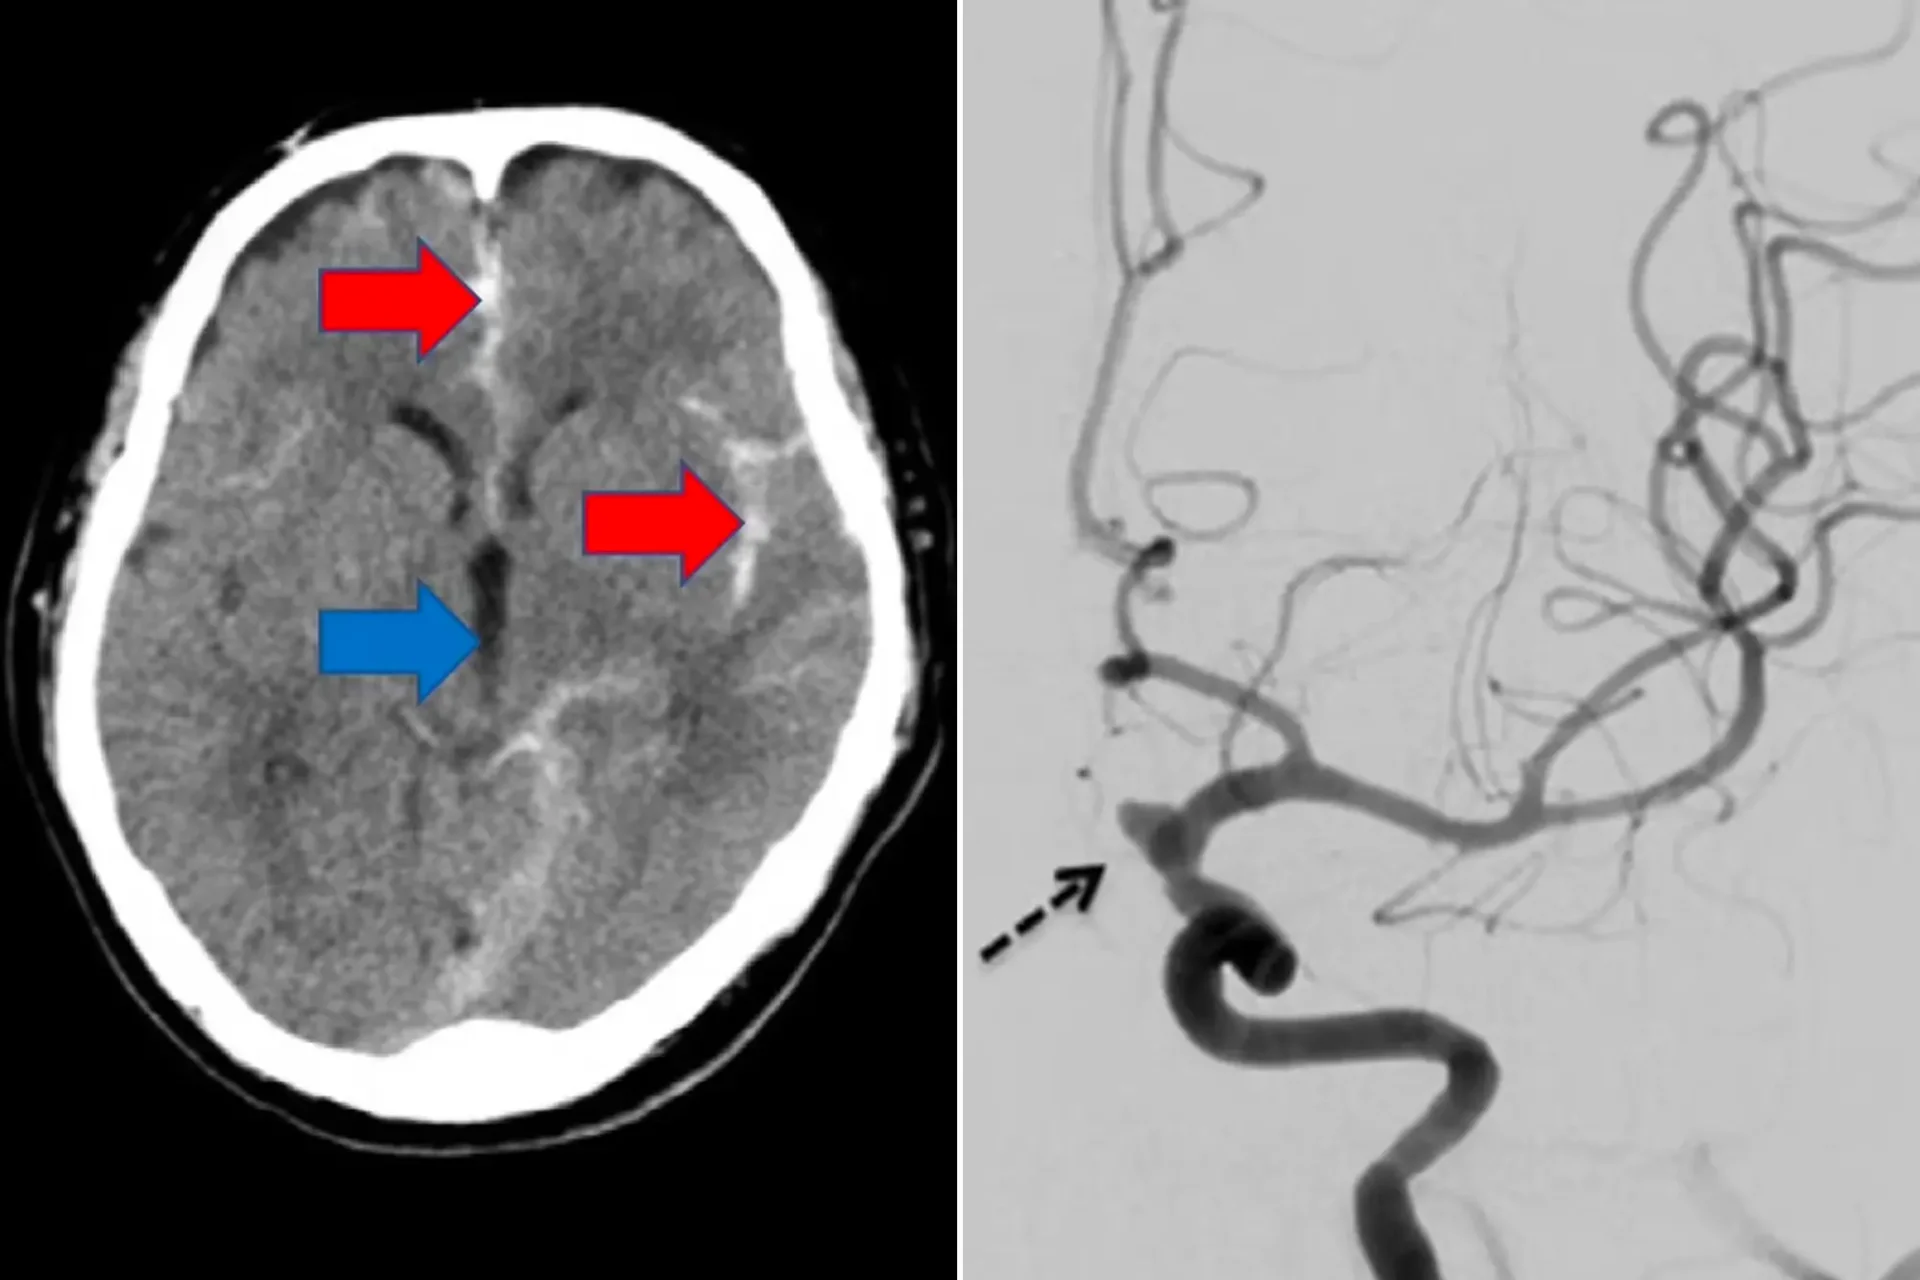

Δυστυχώς, όπως αναφέρεται στη σχετική δημοσίευση στο επιστημονικό περιοδικό “Journal of Stroke and Cerebrovascular Diseases”, ο άντρας υπέστη υποαραχνοειδή αιμορραγία –μια μορφή εγκεφαλικού κατά το οποίο η αιμορραγία συμβαίνει στους γεμάτους υγρό χώρους τους εγκεφάλου– που συνήθως παρατηρείται έπειτα από έντονη σωματική προσπάθεια.

Οι γιατροί έκαναν αξονική τομογραφία στον εγκέφαλό του, με τα αποτελέσματα των εξετάσεων να επιβεβαιώνουν ότι είχε υποστεί εγκεφαλικό, κατάσταση που θα μπορούσε να αποβεί μοιραία.